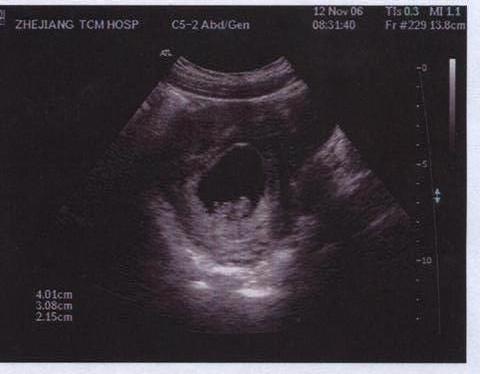

This is the third picture of baby Niall/Tiffany, Now the baby truely looks like a baby, the eyes are closer together, the head is the right shape, I am going to love this baby very much. we still don't know if the baby is a boy or girl, the hospital will not tell us, but I have the feeling it's a boy.